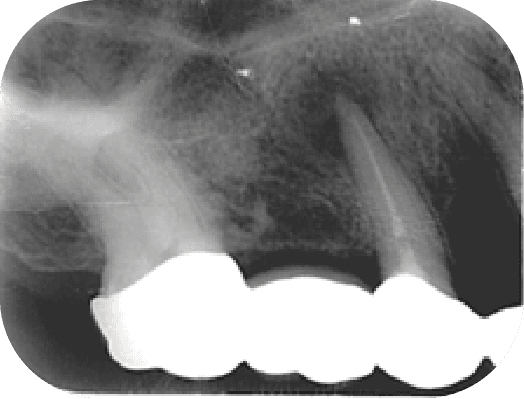

左圖為還沒治療前,根管空間寬大(黑黑的部分),就算完成傳統治療牙根也會比較脆弱,右圖為顯微鏡輔助牙根再生術後兩年,牙根厚度變厚,牙齒使用年限大幅提升

上圖為還沒治療前,根管空間寬大(黑黑的部分),就算完成傳統治療牙根也會比較脆弱,下圖為顯微鏡輔助牙根再生術後兩年,牙根厚度變厚,牙齒使用年限大幅提升